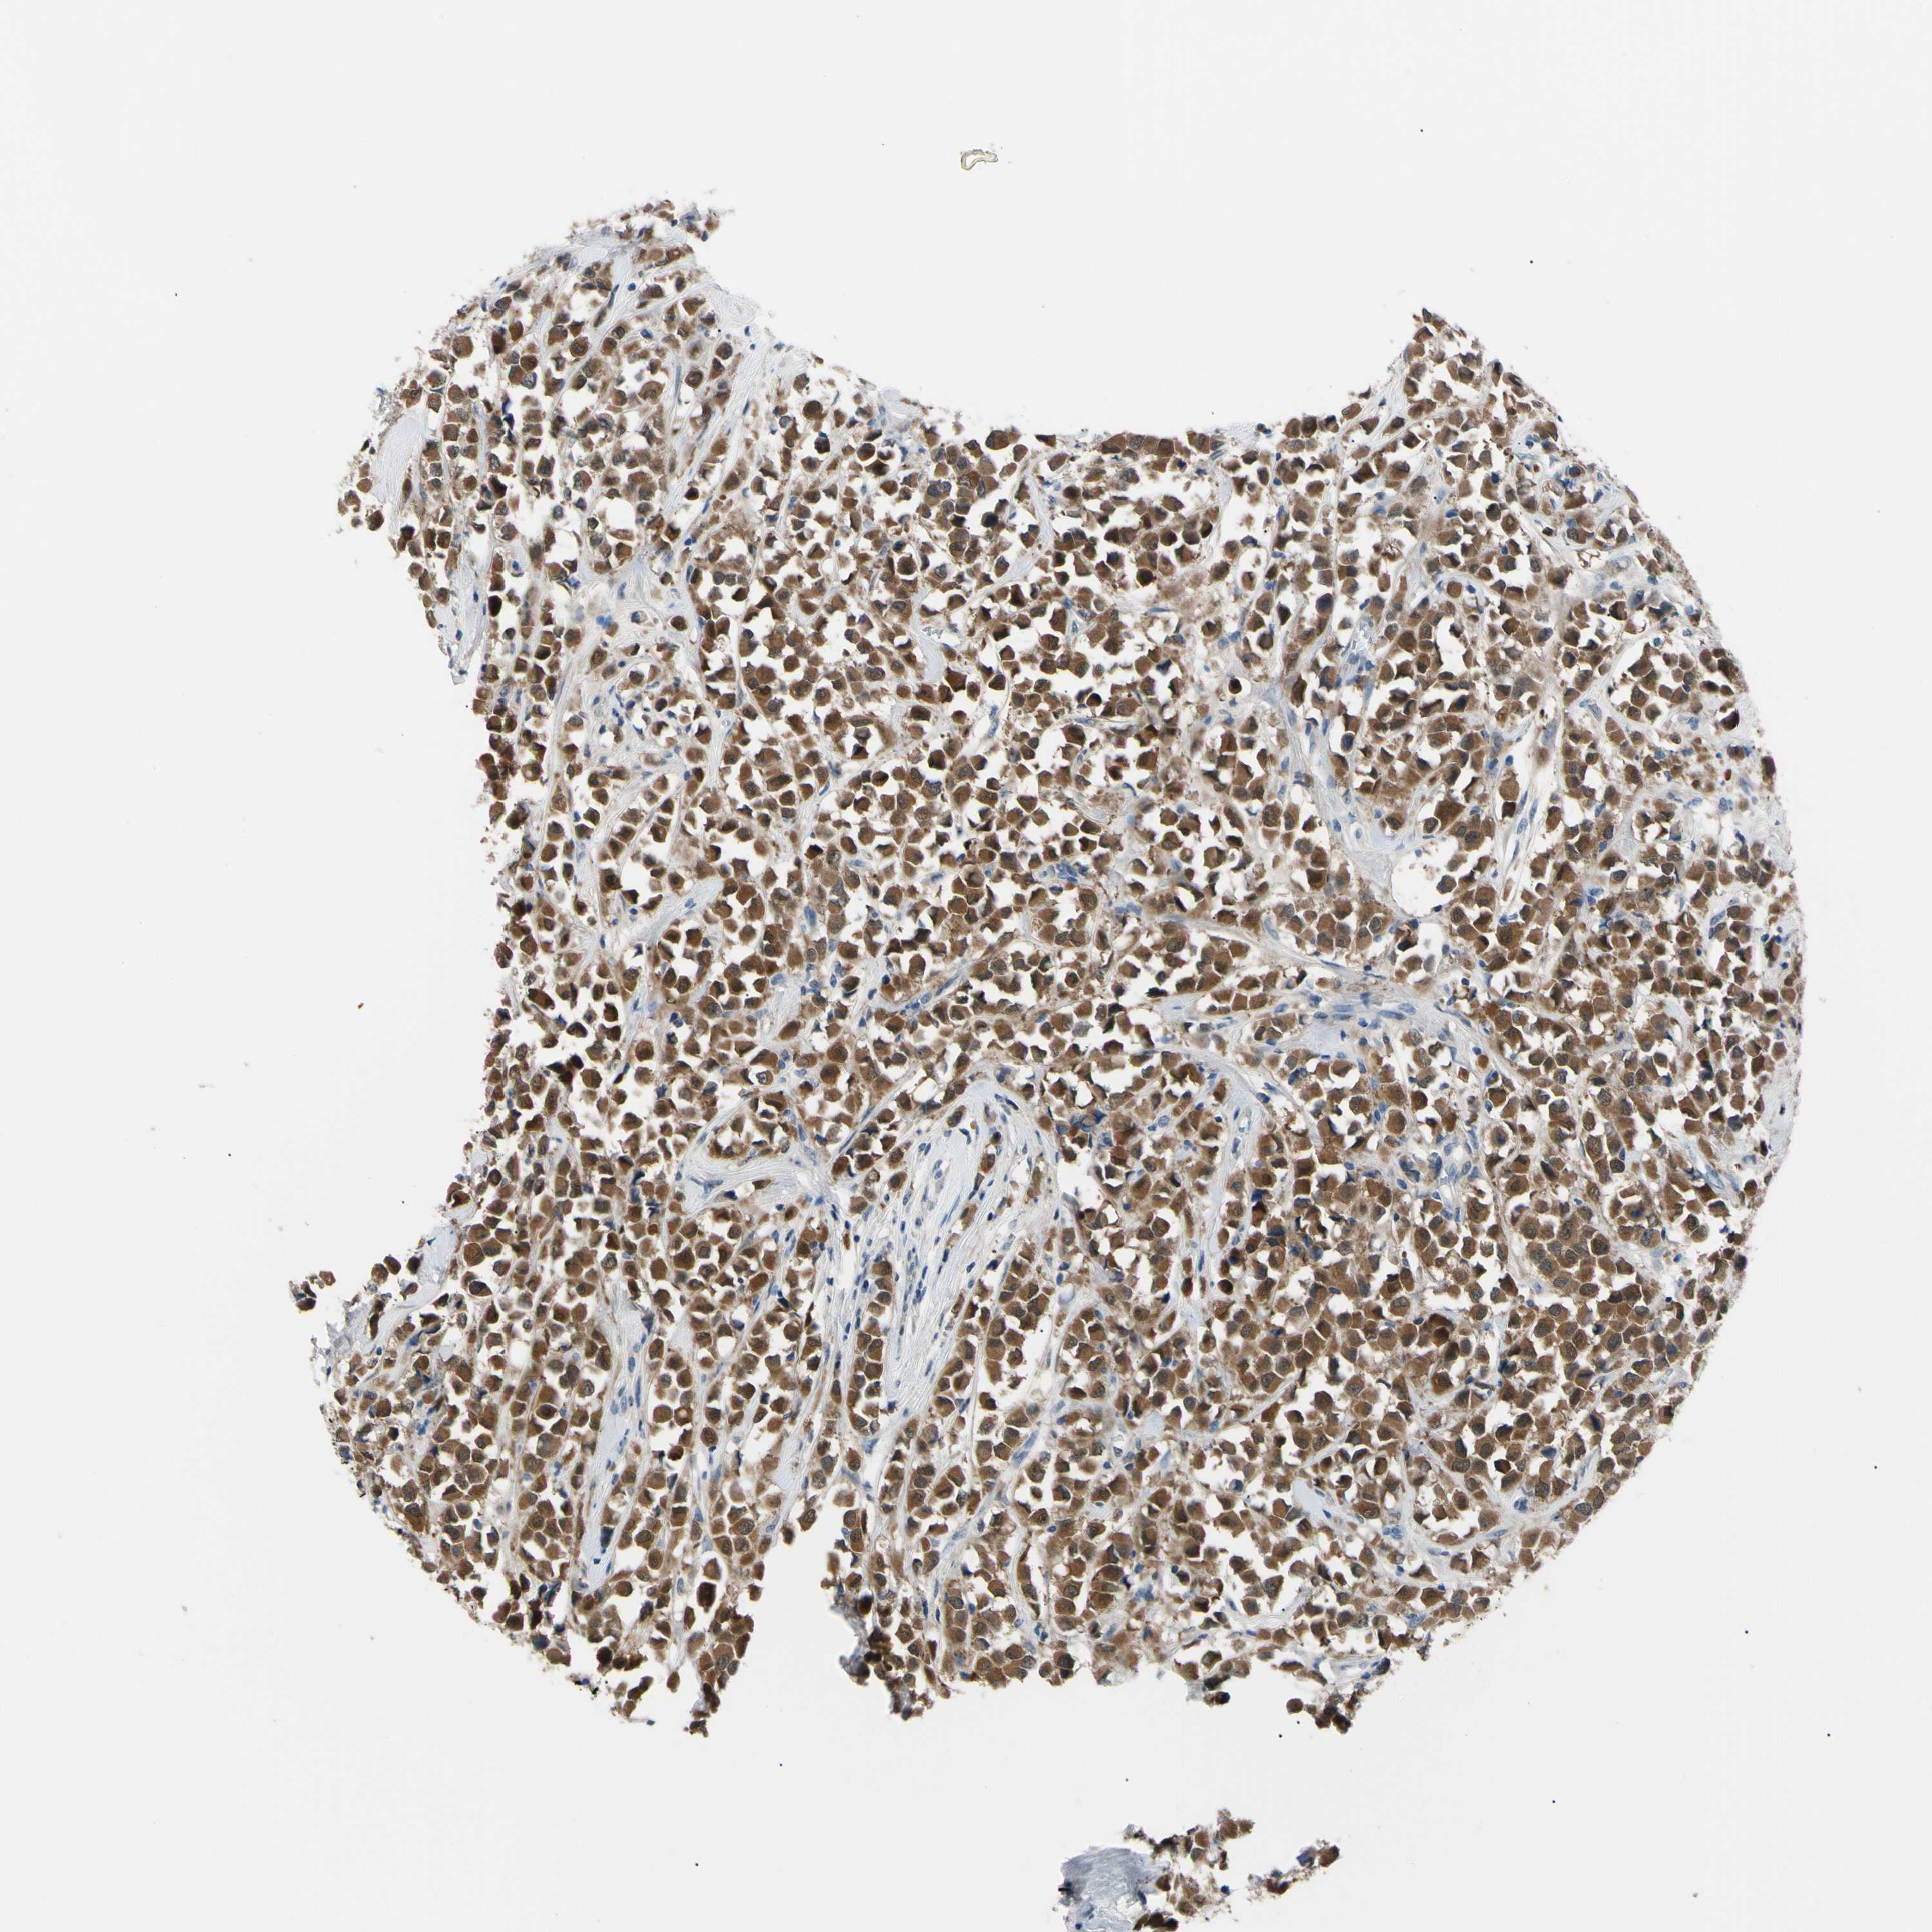

BRCA TCGA BRCA VALIDATION PROTEIN EXPRESSION

Breast cancer

Human cancer

NOL3 is potential prognostic, high expression is unfavorable in Breast Invasive Carcinoma (TCGA)